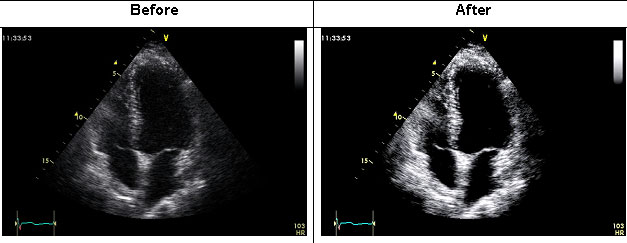

Results: Echocardiographic image before and after the use of the algorithm.

It is noticeable that the use of the algorithm significantly improved the ability to discriminate left ventricular endocardial cavity borders.